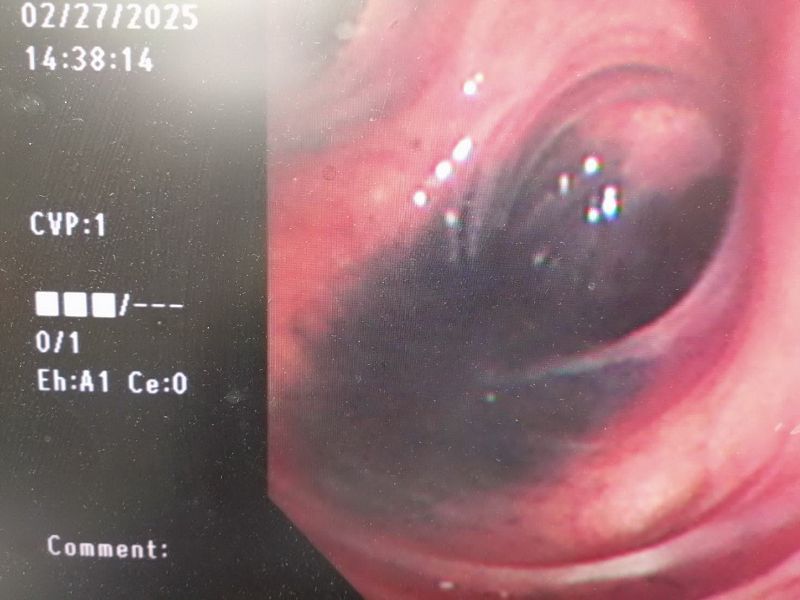

楊老先生有陳舊性肺結核、憂鬱症等病史且長期吸菸,他一生戎馬並未從事礦工、工兵或陶瓷等易接觸粉塵的職業。因其肺炎位於右上肺葉,是肺結核的好發區域,考量陳舊性肺結核也有可能在身體狀況不佳的情況下復發,主治醫師認為需進一步取得痰液標本進行抹片與培養檢查,以確定診斷並據以治療。然而,患者高齡且咳痰無力,即使護理人員努力協助,仍抽不出痰液,無法取得檢體。臺北榮總桃園分院胸腔內科醫師陳家豪遂決定進行支氣管鏡肺泡沖洗術,以取得痰液檢體送肺結核檢查。支氣管鏡檢查發現,患者支氣管壁多處出現大片黑色黏膜,醫學上稱為「Anthracosis」(黑肺病),常見於煤礦工人、從事煤炭工作以及長期吸菸者。黑肺病會造成長期咳嗽、呼吸困難及肺功能衰退,治療上最重要的是遠離致病原因、戒菸,以及使用支氣管擴張劑等藥物。